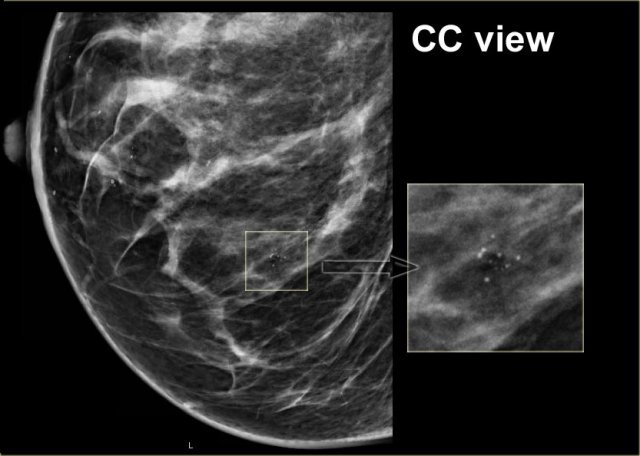

Here another example of the tatoo-sign.

First notice that there are some calcifications that are clearly located within the skin (arrows).

The cluster calcifications on the MLO-view has the exact configuration as the cluster on the CC-view (next image).

On the CC-view the configuration of the microcalcifications is exactly the same.

If these calcifications were located in the centre of the breast they should have a different configuration, because the projection is different.

Only when calcifications are located within the skin their configuration stays the same.